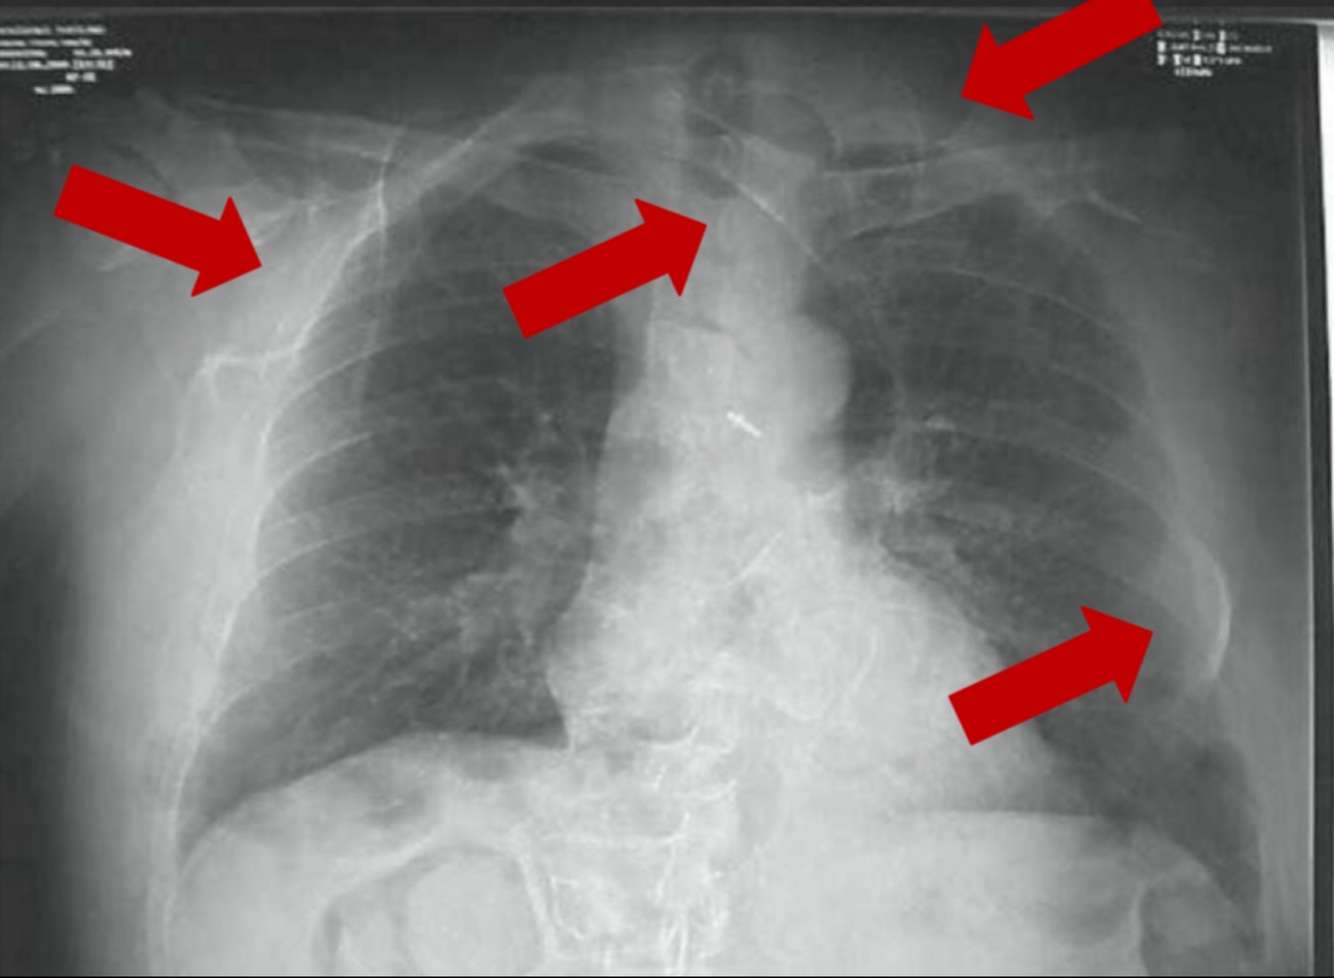

How can this image be improved?

• Use appropriate sized IR • Center body part to IR • Parallel collimation • Tighter collimation • Proper patient positioning